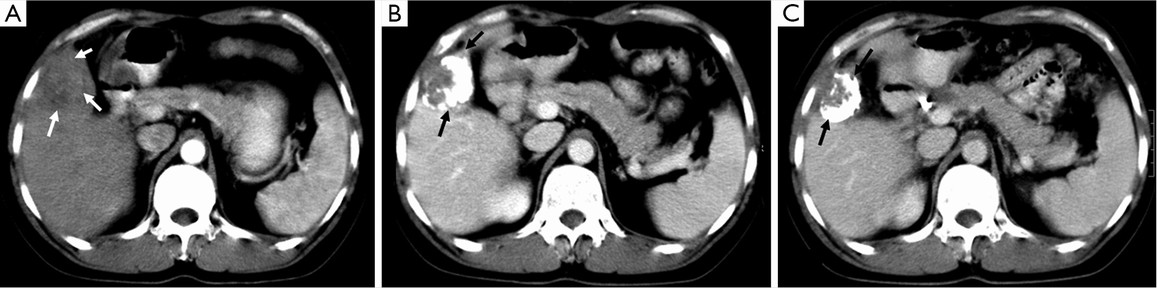

Lipiodol® (Lipiodol® Ultra Fluid, Guerbet, Roissy, France), also known as ethiodized oil, is an oily contrast medium with an iodine content of 38 percent by weight. Its iodine concentration is 480 mg/mL. The viscosity of Lipiodol at 37 °C is approximately 25 mPa.s and its density is 1.28. It consists of a mixture of di-iodinated ethyl esters of fatty acids from poppy seed (Papaver somniferum L.) oil (31). Basically, Lipiodol® combines four characteristics that explain its wide use in TACE procedures: (I) it is opaque to X-rays; (II) it can be used for drug delivery purposes, with substantial versatility regarding the therapy that can be delivered (including immune or gene therapies); (III) it has tumor-seeking properties; (IV) it induces a transient and plastic embolization of tumor microvessels (Figure 5) (76-79). It is not designed to achieve complete and permanent arterial occlusion, as it is eventually washout from the target organ/area. When selectively injected into the hepatic artery, Lipiodol® selectively remains more in tumor nodules for several weeks to over a year due to a siphoning effect from hypervascularization of the tumor vessels and the absence of Kupffer cells inside tumor (Figures 6,7). Non-clinical studies with fluorescent tracer have shown that, in the case of exclusive arterial embolization, the drop in the peribiliary plexus blood pressure would allow portal perfusion of the liver tumor. Conversely, because of its oily nature, Lipiodol® distributes in both the tumor artery branches and the peritumor portal venules, thus allowing transient dual embolization (79).

Patients with heterogeneous Lipiodol® uptake on CT scan have higher tendency of recurrences during the follow-up period than those with homogeneous uptake. The degree of Lipiodol® labeling has been found to be an independent prognostic factor (83,84). While Lipiodol® has been widely adopted in TACE protocols, it may also mask assessment of residual vascularity on CT imaging following therapy, thereby requiring routine follow-up with contrast enhanced MRI.